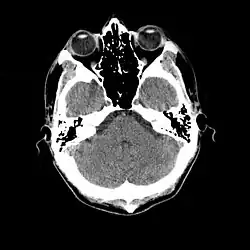

- 1976

- La tomografía computarizada craneal (TC, inventada en 1972) demostró ser una excelente herramienta para diagnosticar neoplasias cerebrales en niños, incluidas las encontradas en la esclerosis tuberosa.[46]

- 1987

- La resonancia magnética se consideró superior a la TC en cuanto a sensibilidad y especificidad. En un estudio de quince pacientes, identificó nódulos subependimarios que proyectaban hacia los ventrículos laterales en doce pacientes, distorsión de la arquitectura cortical normal en diez pacientes (correspondiente a tubérculos corticales), ventrículos dilatados en cinco pacientes, y distinguió un astrocitoma conocido de nódulos subependimarios benignos en un paciente.[53]

- Se encontró que la imagen por RM era capaz de predecir la gravedad clínica de la enfermedad (epilepsia y retraso del desarrollo). Un estudio de 25 pacientes encontró una correlación con el número de tubérculos corticales identificados. En contraste, la TC no fue un predictor útil, pero fue superior en la identificación de lesiones calcificadas.[54]